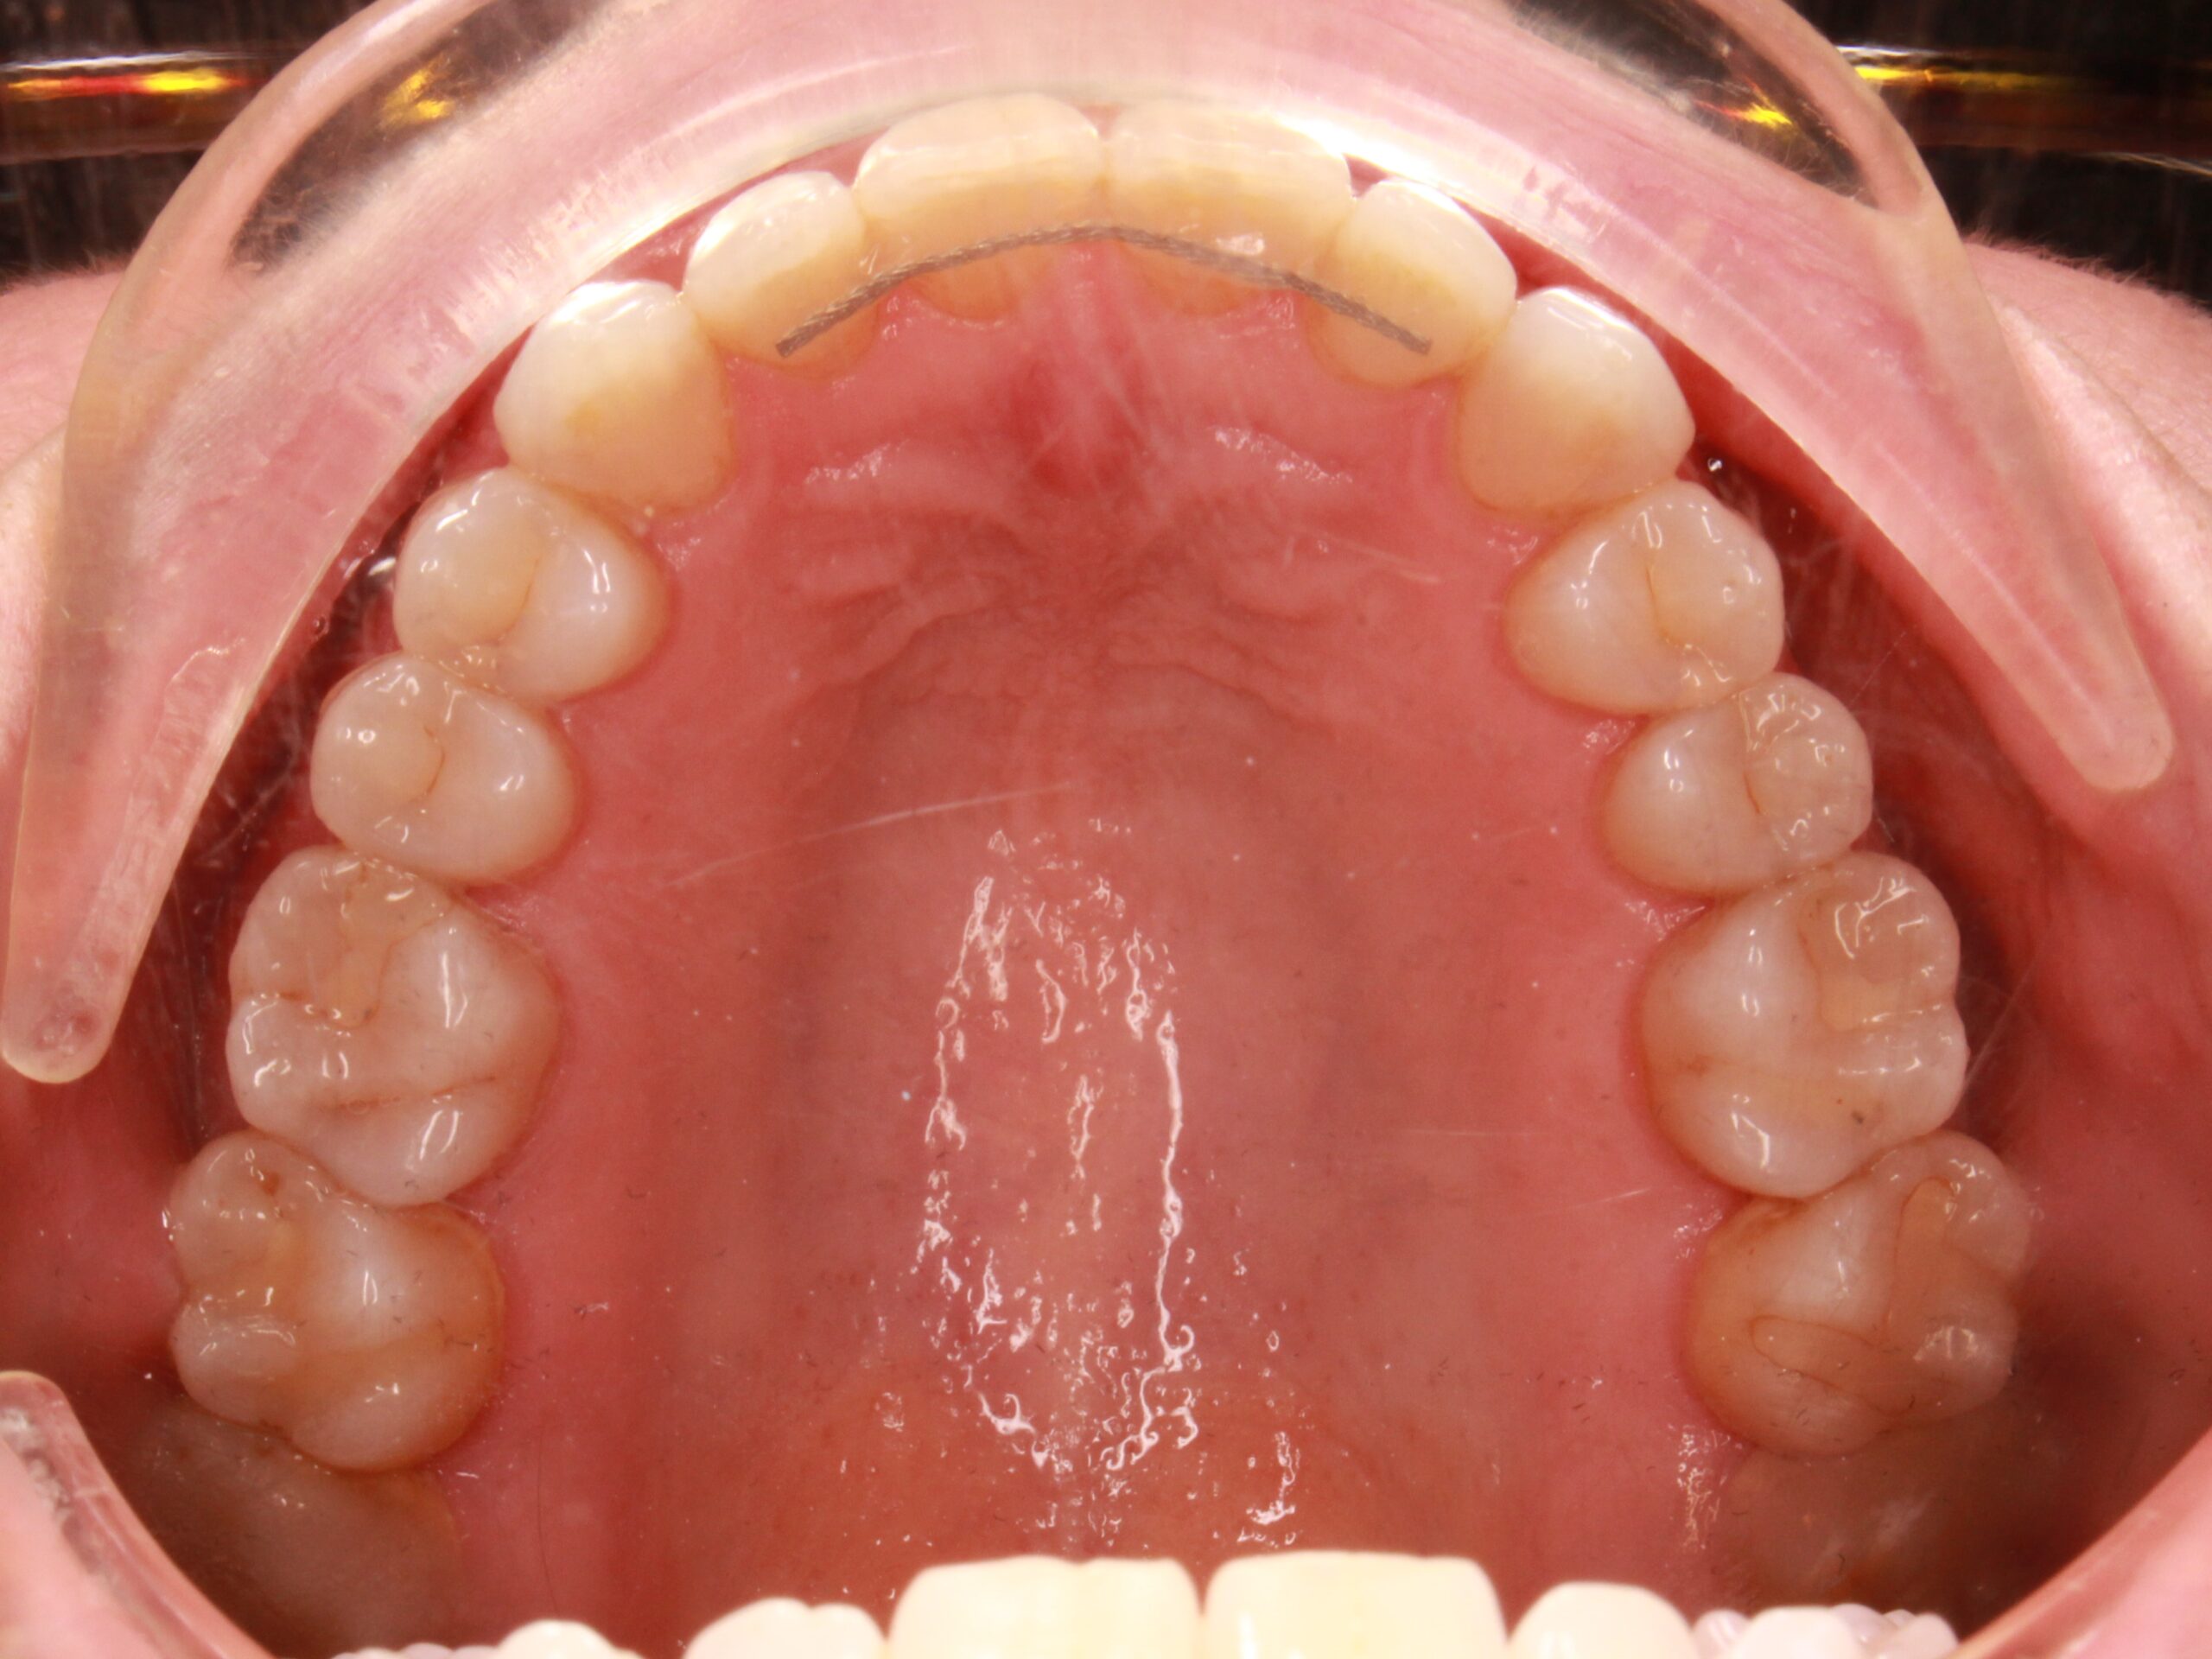

In fact, when the torque correction of posterior sectors was expressed, some palatal cusps descended more than desired, which generated a scarce lateral perspective of stable occlusion, for which the refinement was planned in the following way:

After 8 months of the primary treatment plan and the refinement, it was possible to observe a fulfillment of the objectives demanded by the patient and clinically marked at the time of the initial diagnosis.